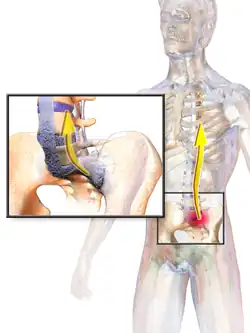

Illustration depicting ankylosing spondylitis

The signs and symptoms of ankylosing spondylitis often appear gradually, with peak onset between 20 and 30 years of age.[11] Initial symptoms are usually a chronic dull pain in the lower back or gluteal region combined with stiffness of the lower back.[12] Individuals often experience pain and stiffness that awakens them in the early morning hours.[11]

As the disease progresses, loss of spinal mobility and chest expansion, with a limitation of anterior flexion, lateral flexion, and extension of the lumbar spine are seen. Systemic features are common with weight loss, fever, or fatigue often present.[11] Pain is often severe at rest but may improve with physical activity. Inflammation and pain may recur to varying degrees regardless of rest and movement.

AS can occur in any part of the spine or the entire spine, often with pain localized to either buttock or the back of the thigh from the sacroiliac joint. Arthritis in the hips and shoulders may also occur. When the condition presents before the age of 18, AS is more likely to cause pain and swelling of large lower limb joints, such as the knees.[13] In prepubescent cases, pain and swelling may also manifest in the ankles and feet where heel pain and enthesopathy commonly develop.[13] Less common occurrences include ectasia of the sacral nerve root sheaths.[14]